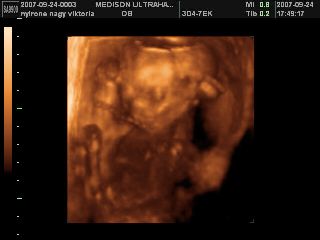

Na megjöttünk az uh-ról, 17 órára volt időpontunk, de majd fél órát csúszott a dolog, mert a doki később tudott bejönni! Minden rendben van, mindene magvan, annyi, amennyinek lennie kell, normál a szíve, a vesék rendben, gyomortelítődés van, méhlepény a fundusban, köldökzsinór 3 erű, viszont nem igen látszott, hogy milyen nemű! A doki szerint inkább lány, mint fiú, de egyáltalán nem mondta egyértelműre, és nem is látszott, összeszorította a lábacskáit a kis szégyenlős! :lol: De a lényeg az, hogy egészséges, és végre láttam az arcát is! :D